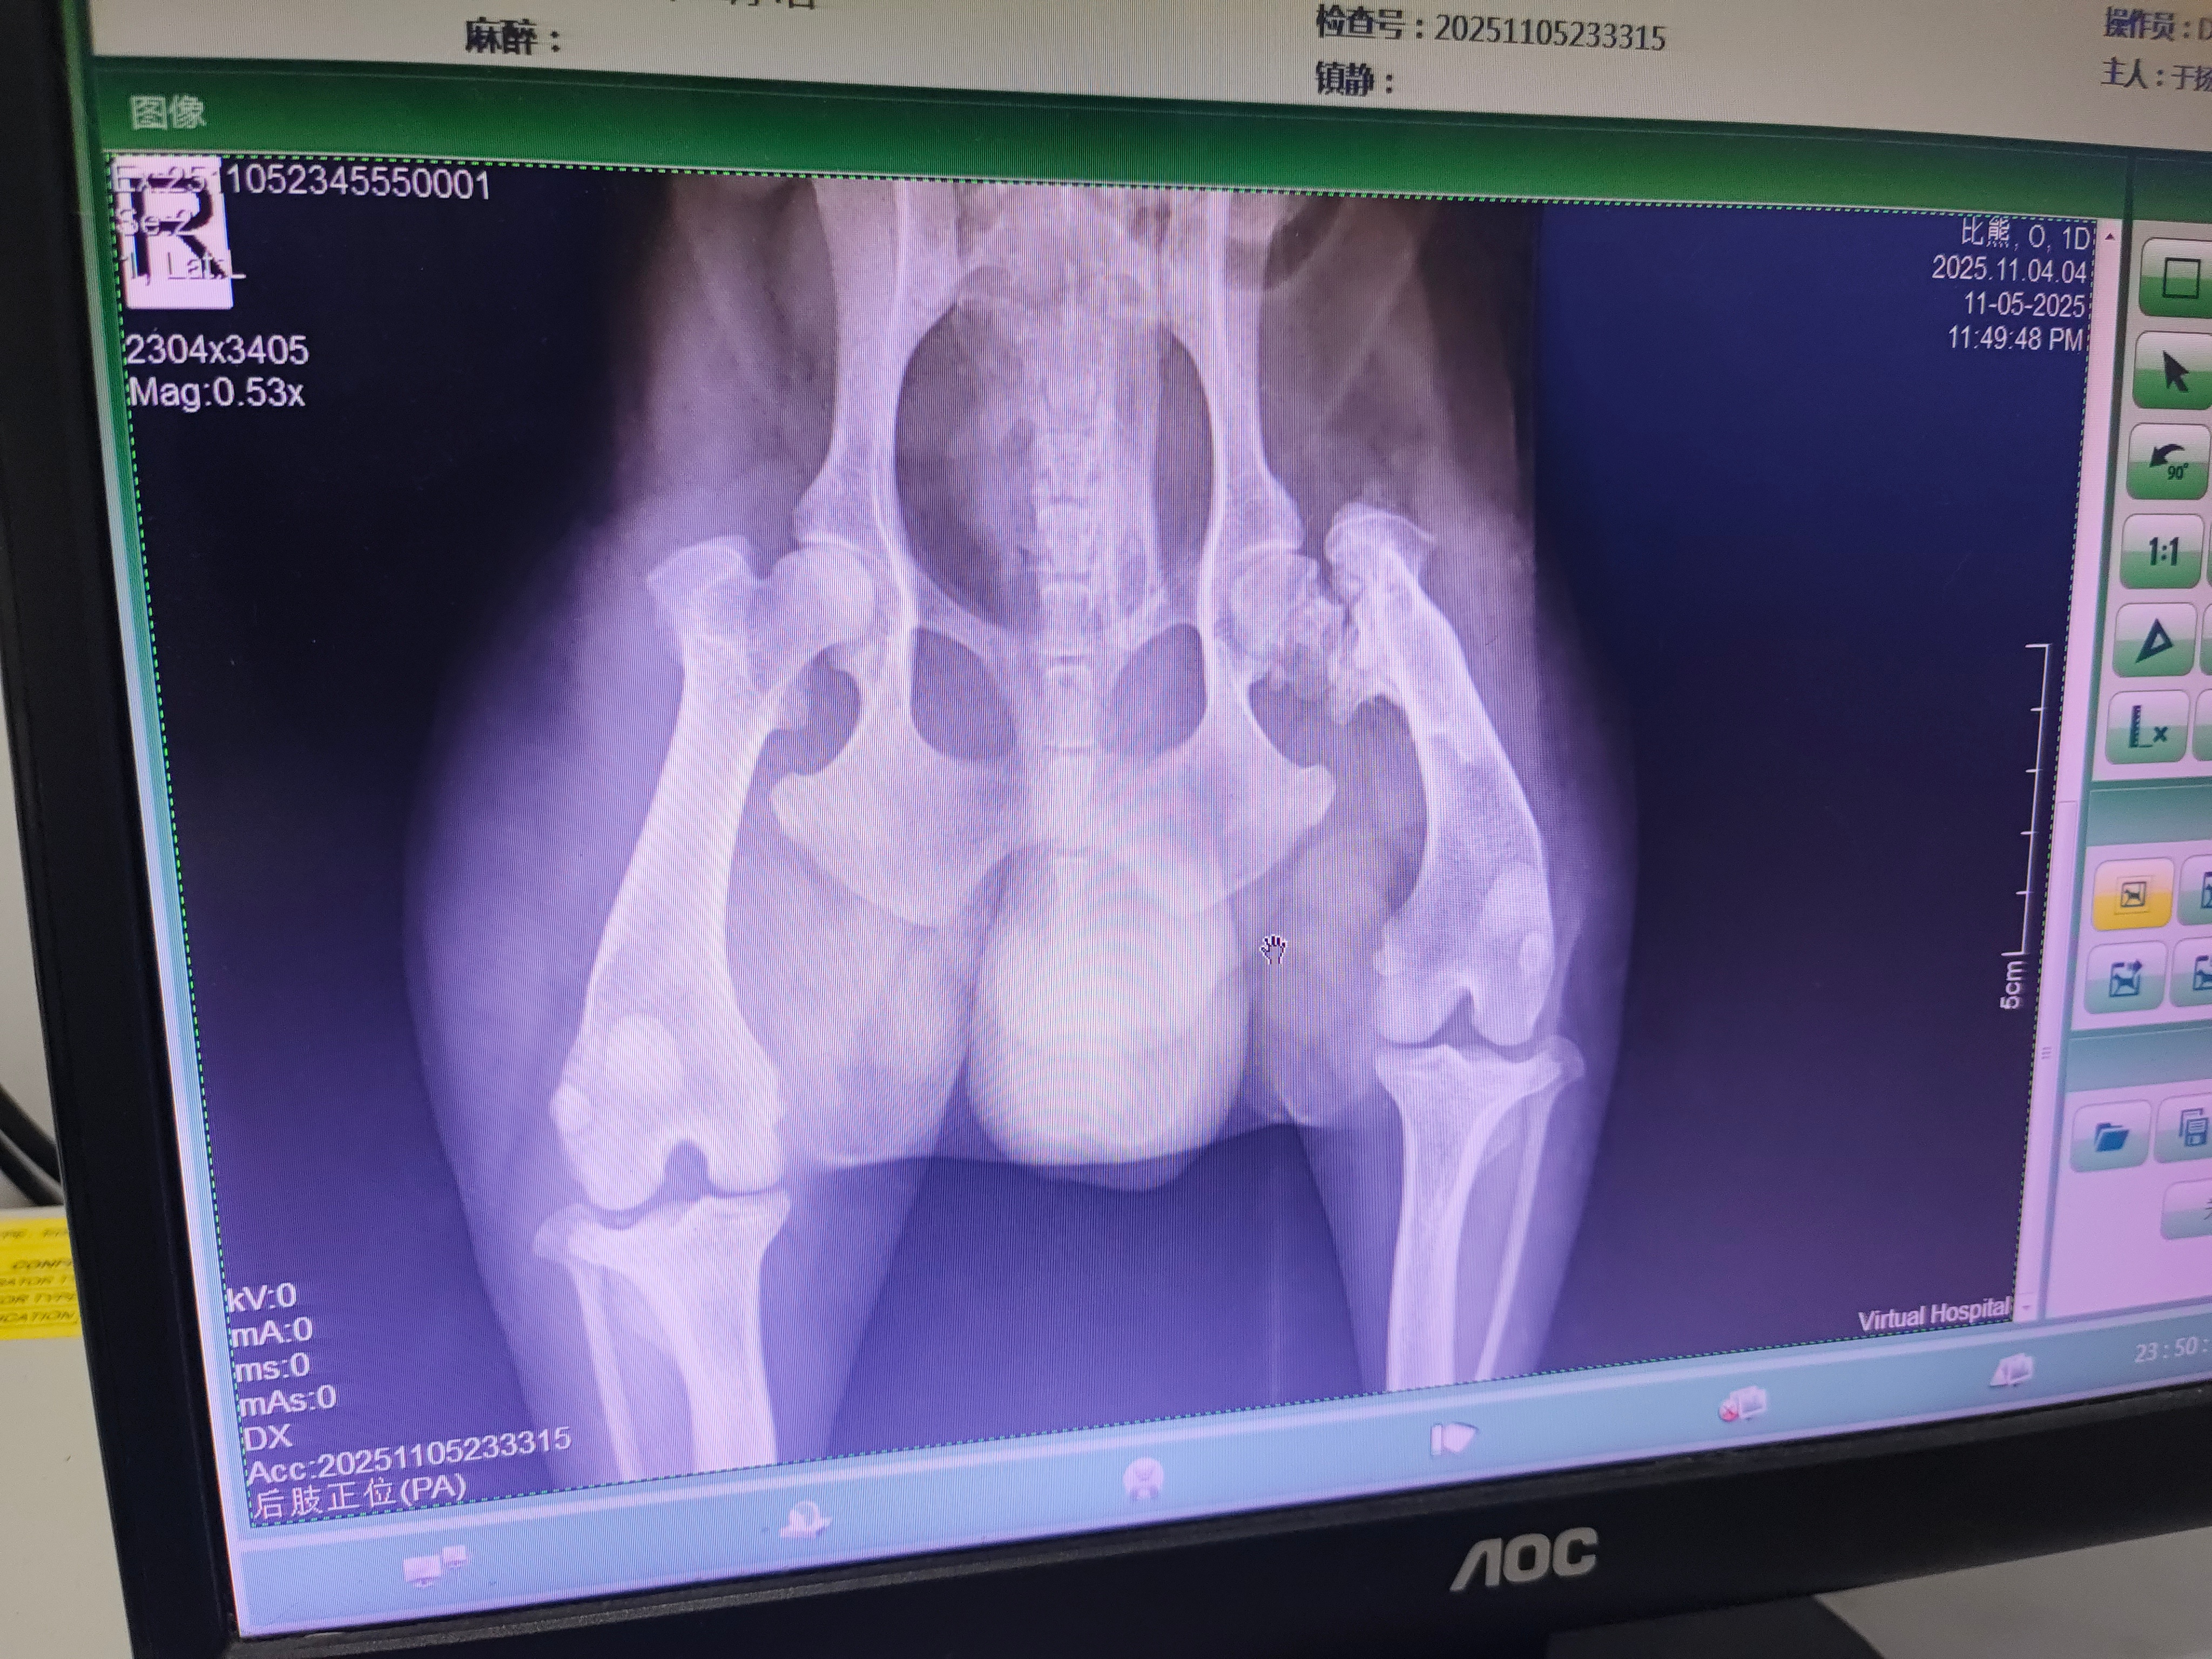

不救不知道,这狗狗右腿上的伤不严重,但已经有段时间了,医生说里面已经烂了,有小部分皮肉都分离了,有的地方皮肤发黑了,甚至都不一定保得住,肯定不是新伤了。而且左腿的股骨头还骨折了,想治好,哪怕只是普通的手术取出断了的股骨头,也得有个几千块。而且这小家伙年纪挺大了,至少15岁的样子,也不知道能撑多久,能不能挺住。但它真的很懂事,知道我们在救他,不哼也不叫,乖乖配合……我们猜测有可能是伤了之后被主人……唉,挺无语的……